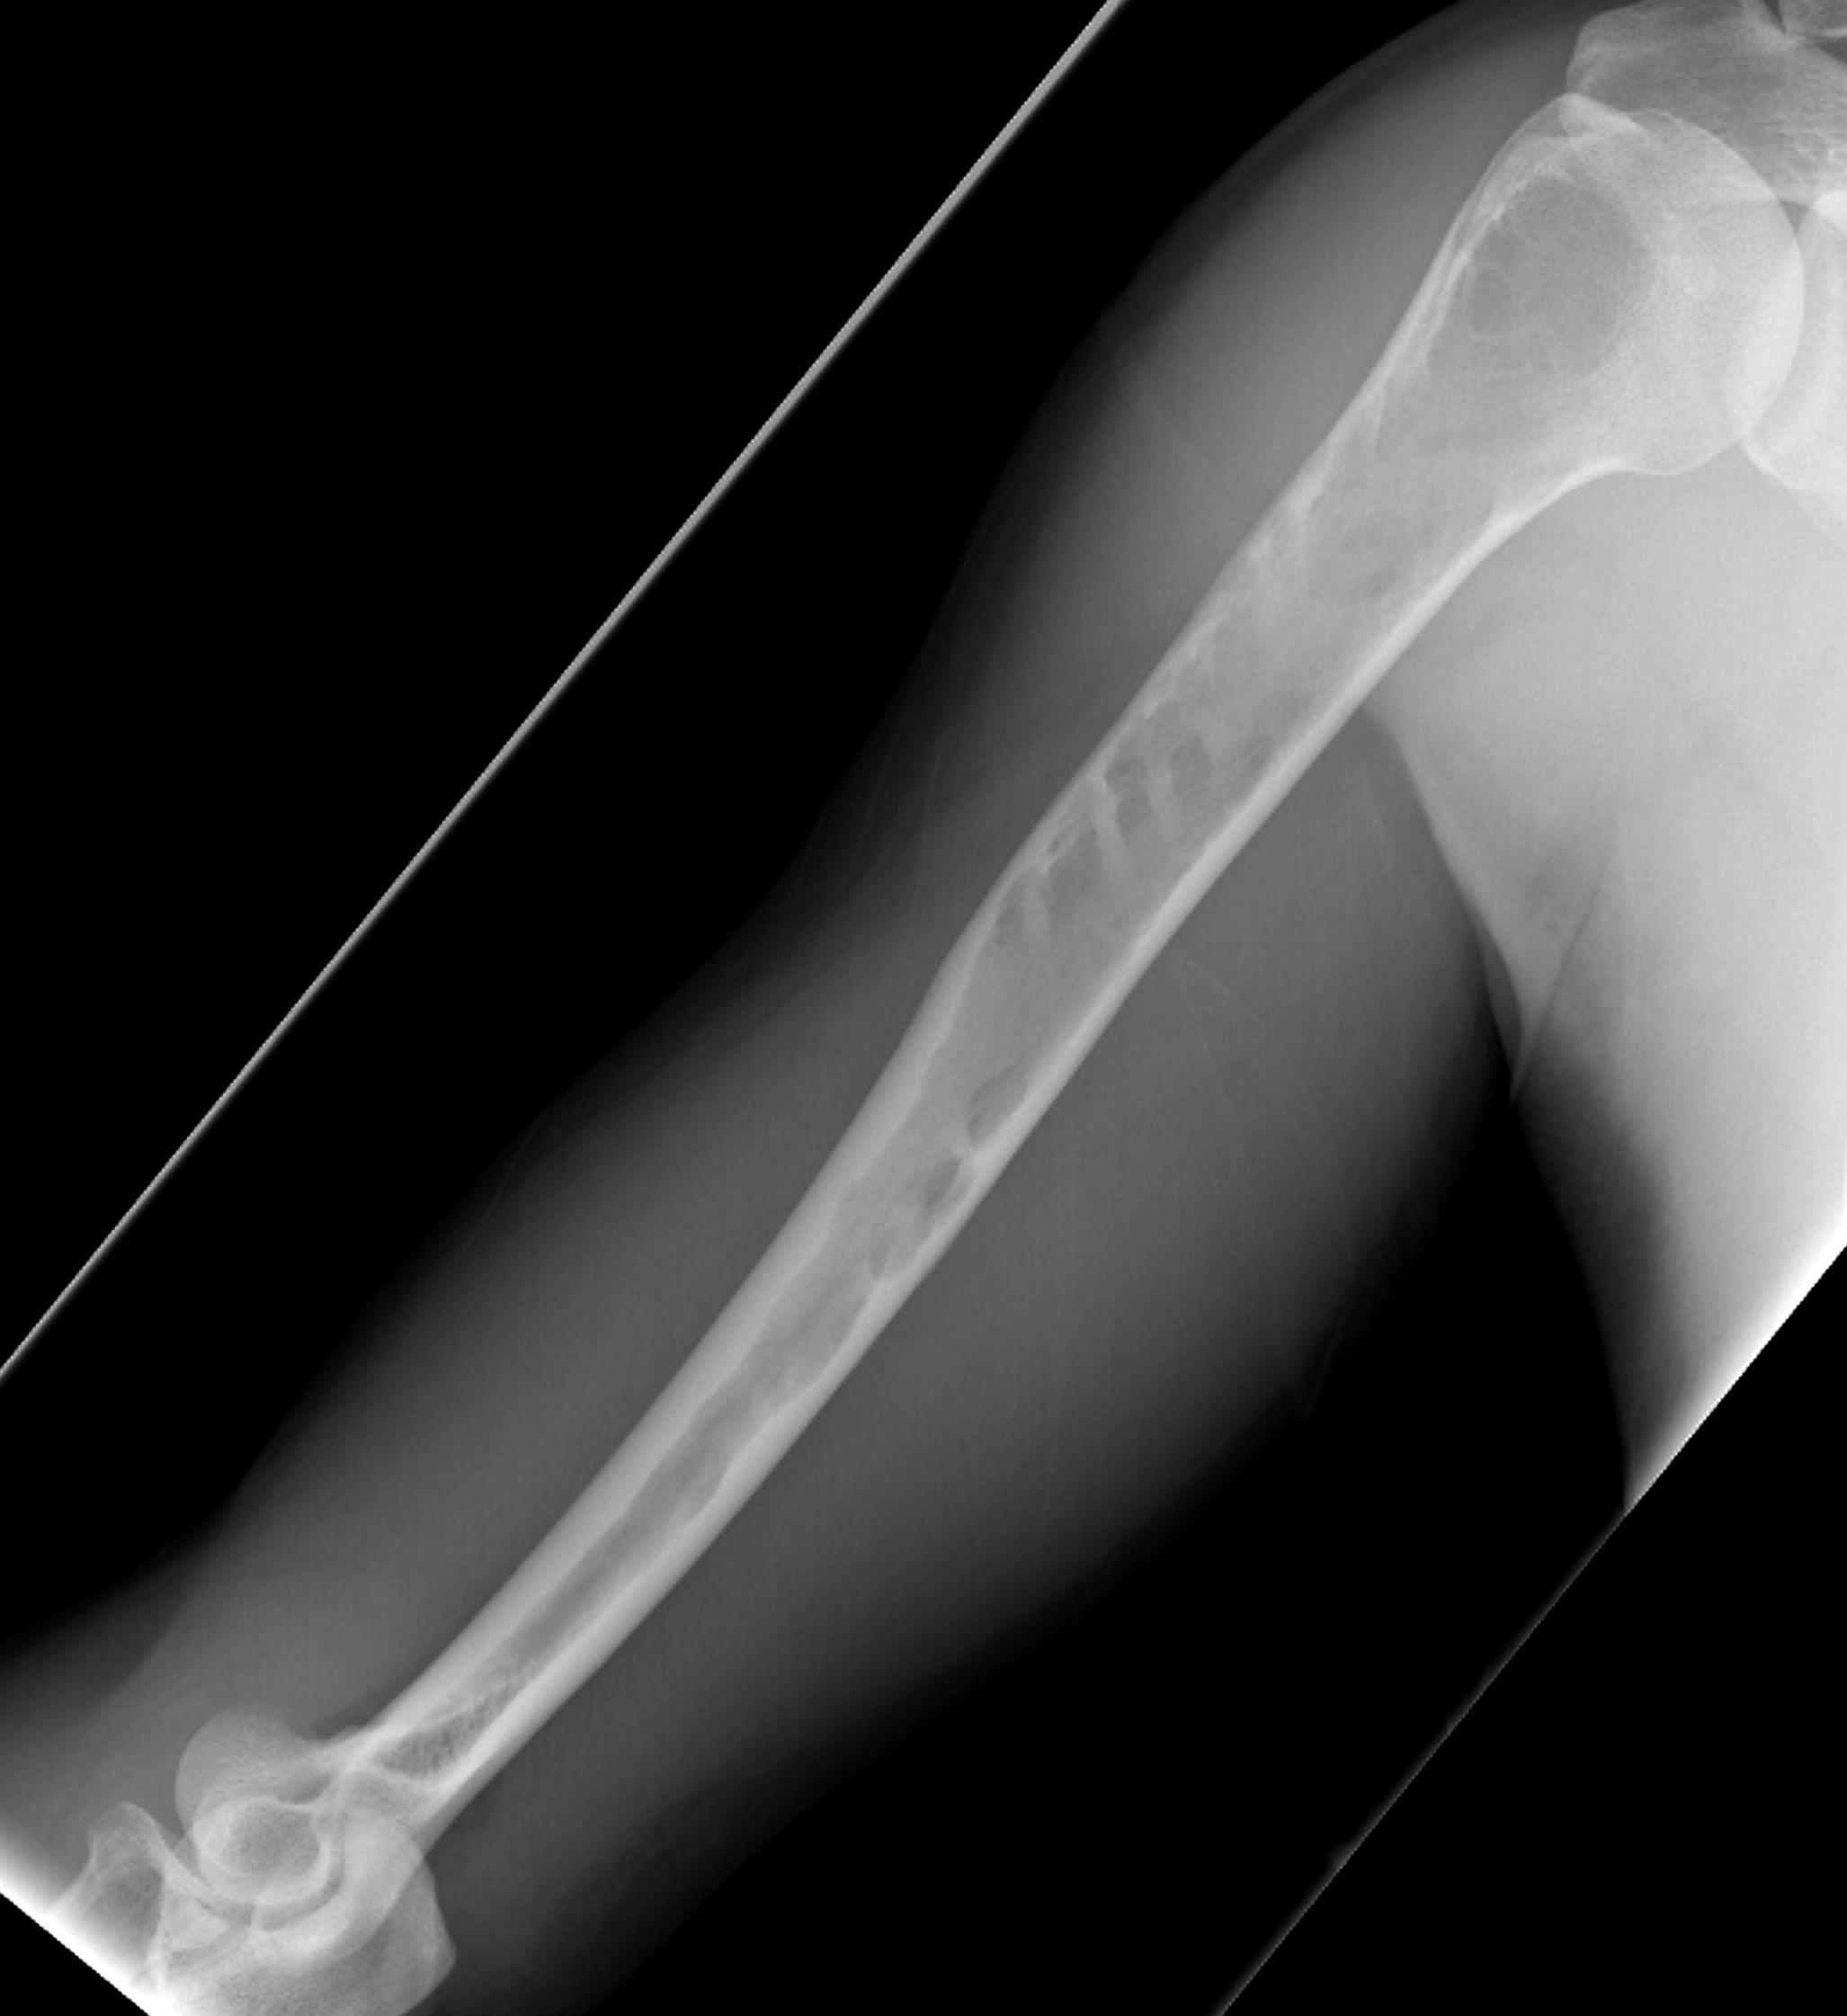

X-ray

1. Punched out lytic lesions

- axial and appendical skeleton

- widely disseminated

- soap bubble appearance

- no sclerotic reaction

2. Diffuse osteopenia

- in 15% to 25% of patients, no discrete lysis occurs

- diffuse osteopenia and osteoporosis are the only skeletal manifestations

3. Vertebrae Plana

4. Pathological Fracture

5. Pepper pot skull

Skeletal survey

Xray

- skull / spine / humerus / femurs / pelvis / chest & ribs

- low sensitivity

- only detect lesions with > 30% cortical destruction